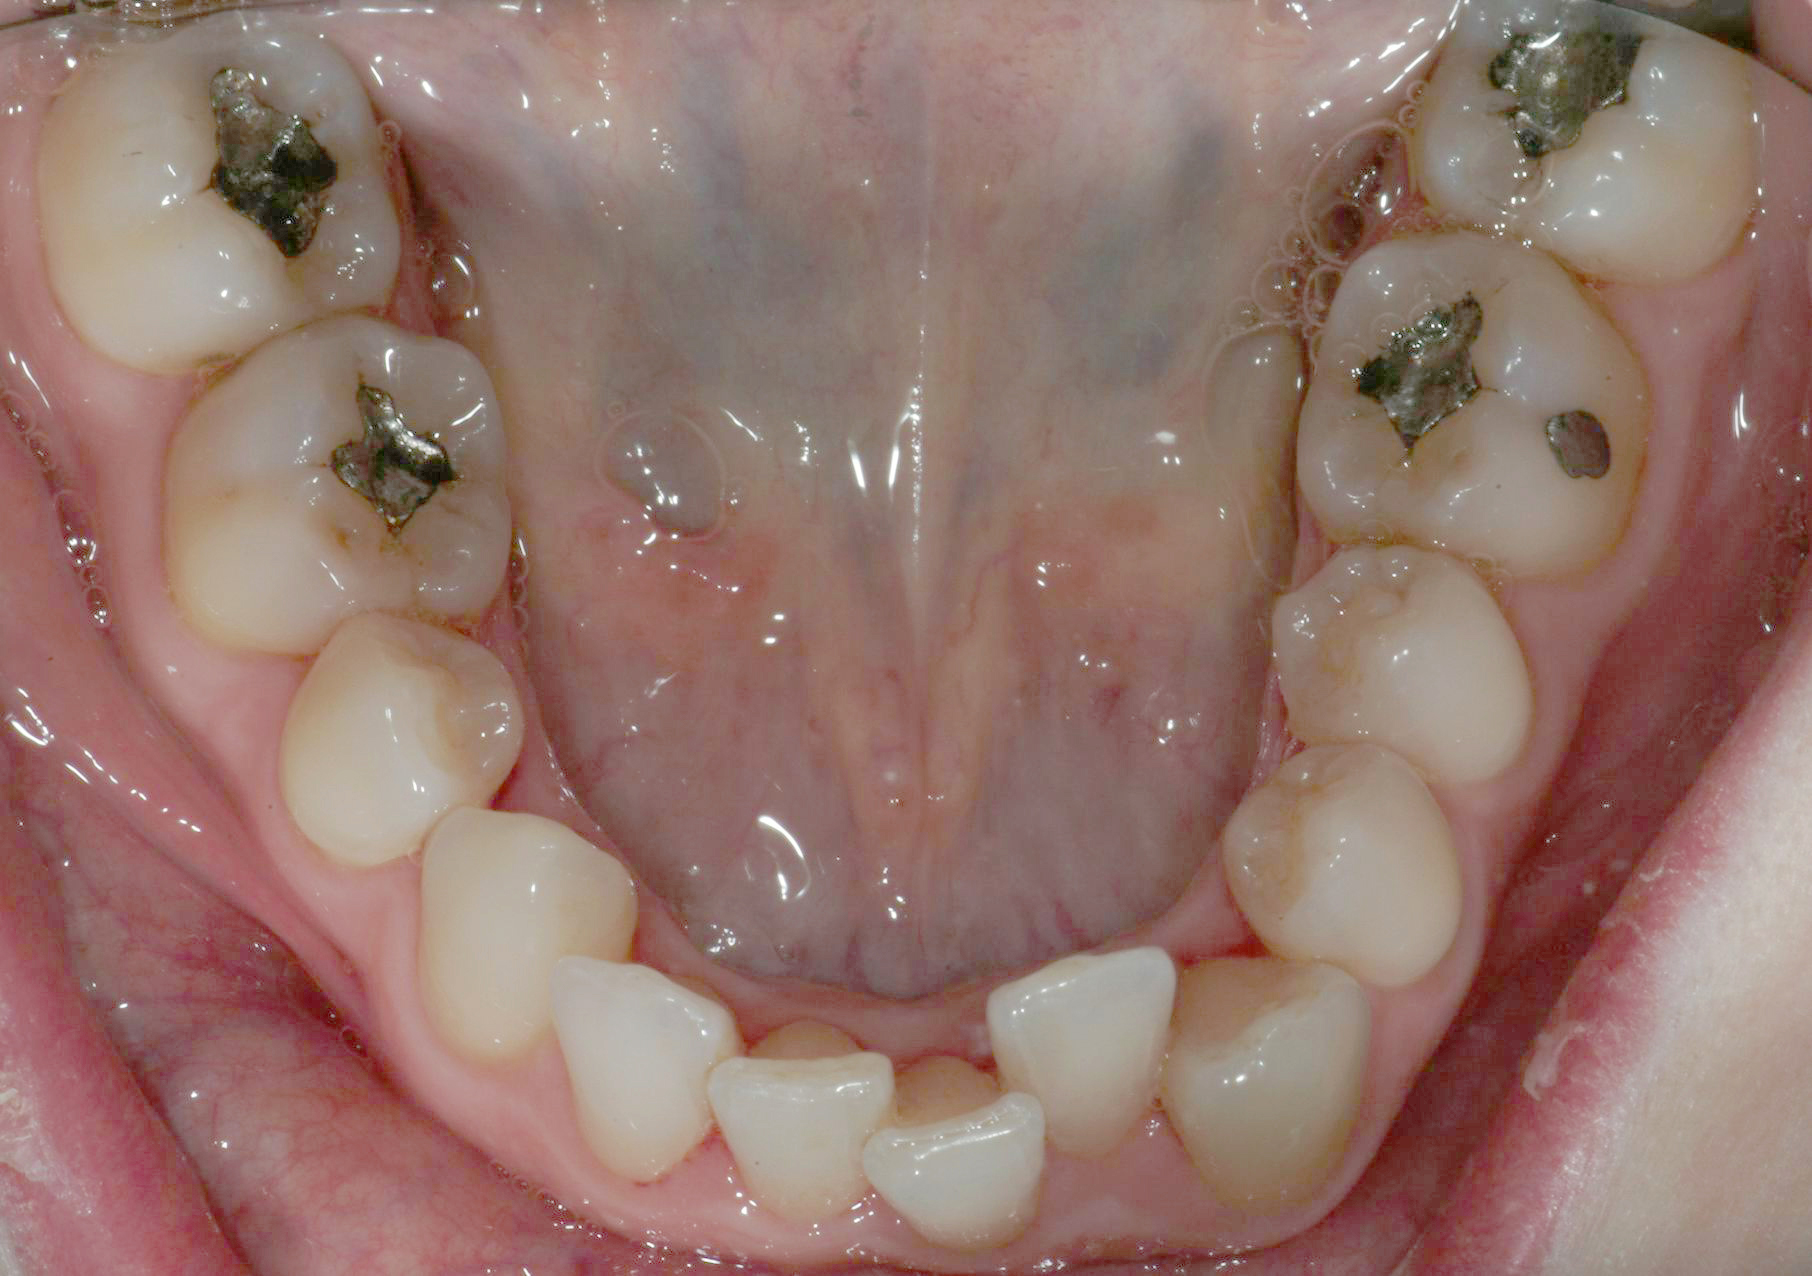

Una paziente di sesso femminile, 38 anni, già trattata ortodonticamente presso altra sede con apparecchiatura fissa a entrambe le arcate in età adolescenziale senza successiva applicazione di alcuna contenzione, si presenta alla nostra attenzione perché insoddisfatta dell’estetica del sorriso; richiede una valutazione per un trattamento ortodontico con apparecchiatura fissa linguale per la presenza di affollamento dentale a entrambe le arcate e difficoltà a mantenere una adeguata igiene orale; si riscontrano agenesia di entrambi gli incisivi laterali superiori (1.2 e 2.2) e del secondo premolare inferiore destro (4.5). Presentiamo la risoluzione del caso mediante trattamento ortodontico estrattivo a entrambe le arcate, eseguito con apparecchiatura linguale invisibile 2D e meccanica asimmetrica e seguito a medio termine da riabilitazione implanto-protesica e contenzione fissa.

Per formulare corretta diagnosi e piano di cura, lo studio del caso ha previsto la raccolta di documentazione completa standard, ovvero fotografie del viso e intraorali (Figure 1a-e), radiografia panoramica e teleradiografia del cranio in proiezione laterale (Figure 2a-b) per la relativa analisi cefalometrica e modelli di studio.

La valutazione clinica e gli esami effettuati confermano la presenza di agenesia degli incisivi laterali superiori (1.2 e 2.2) e del secondo premolare inferiore destro (4.5).

L’analisi ortodontica e la valutazione parodontale, con particolare riferimento alla posizione della radice del canino superiore destro (1.3), distoinclinata e trasposta alla radice del primo premolare (1.4) come evidente dalla radiografia panoramica e dalle immagini intraorali, ci hanno guidati nella programmazione di un trattamento estrattivo asimmetrico a entrambe le arcate.